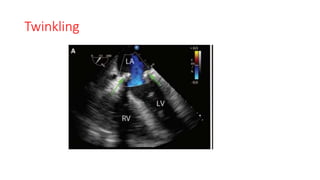

Twinkling

• Used for diagnostic purposes in noncardiac imaging “twinkling”

artifacts are a mosaic of rapidly changing blue and red patches of

color near strongly reflective surfaces resulting in patterns that

imitate abnormal flow.

• Twinkling may be the result of a type of intrinsic scanner noise

dubbed “phase” or “clock jitter.”

• First described in 1996, this artifact may mimic blood flow such as a

regurgitant jet, paravalvular leak, or shunt.

• described in association with echogenic intracardiac foci in the fetal

heart,as well as calcified and noncalcified cardiac valves.

• Vena contracta measurements become inaccurate in association with

a twinkling artifact.

Twinkling • Used fordiagnostic purposes in noncardiac imaging “twinkling” artifacts are a mosaic of rapidly changing blue and red patches of color near strongly reflective surfaces resulting in patterns that imitate abnormal flow. • Twinkling may be the result of a type of intrinsic scanner noise dubbed “phase” or “clock jitter.”

• First describedin 1996, this artifact may mimic blood flow such as a regurgitant jet, paravalvular leak, or shunt. • described in association with echogenic intracardiac foci in the fetal heart,as well as calcified and noncalcified cardiac valves. • Vena contracta measurements become inaccurate in association with a twinkling artifact.